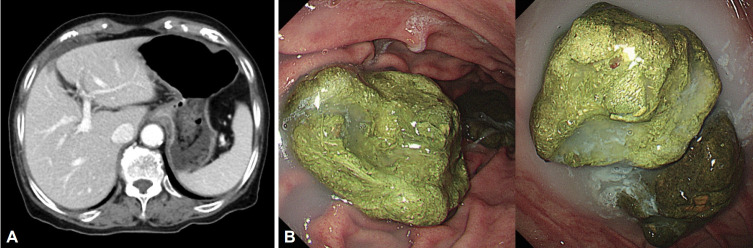

Bezoars, including phytobezoars, trichobezoars, and pharmacobezoars, are accumulations of undigested substances in the gastrointestinal tract. We report three cases of gastric bezoars. Case 1: An 86-year-old woman presented with a one-month history of abdominal pain and vomiting. Esophagogastroduodenoscopy revealed gastric bezoars; consumption of 2 L of cola daily for 2 weeks resulted in complete disappearance of the bezoars. Case 2: An asymptomatic 63-year-old woman underwent esophagogastroduodenoscopy, which revealed a gastric bezoar. Cola spraying and endoscopic lithotomy were ineffective; therefore, the patient underwent laparoscopic removal of the bezoar for management of small bowel obstruction secondary to the bezoar fragments. Case 3: A 6-year-old girl with a history of pica underwent two laparoscopic surgeries 10 months apart for recurrent trichobezoars. We report our treatment approach in three patients who presented with gastric bezoars.